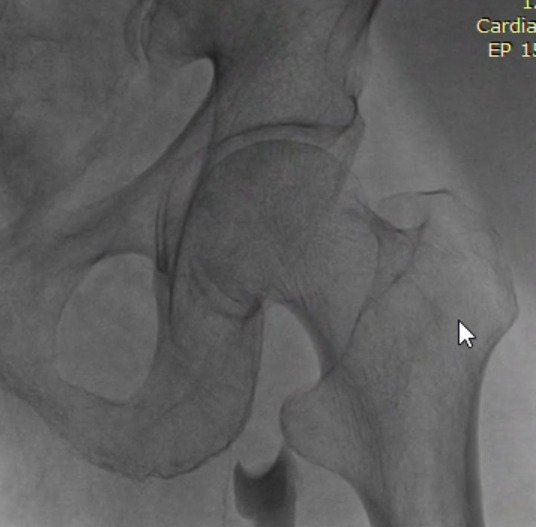

Outcomes observed in patients treated with image-guided, minimally invasive vascular procedures.

Results vary by patient and condition. Images are for educational purposes only.